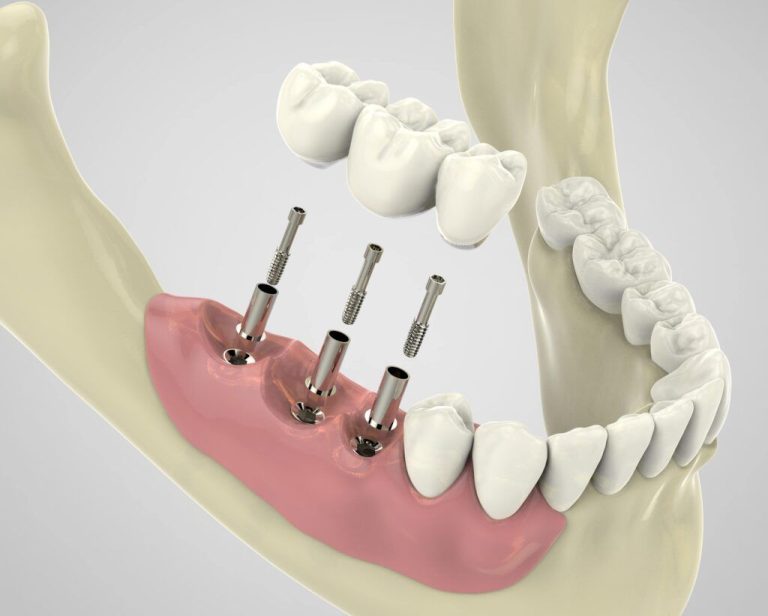

ایمپلنت دندان یک پایه فلزی (معمولاً از جنس تیتانیوم) است که طی یک عمل جراحی در استخوان فک قرار میگیرد و پس از جوش خوردگی با استخوان، نقش ریشه دندان را ایفا میکند. سپس روکش دندان روی آن نصب میشود و عملکرد و زیبایی دندان طبیعی را بازمیگرداند.

۳. کاشت پایه ایمپلنت (فیکسچر) از مراحل انجام ایمپلنت دندان در کرج

- جراحی ایمپلنت: پایه تیتانیومی توسط جراح متخصص و تحت بیحسی موضعی در استخوان فک قرار میگیرد. این مرحله سرپایی و بدون درد است.

- مدت زمان جوش خوردگی: پس از کاشت، باید ۳ تا ۶ ماه صبر کرد تا پایه ایمپلنت با استخوان فک جوش بخورد (فرآیند استئواینتگراسیون).

۴. قرارگیری اباتمنت و قالبگیری از مراحل انجام ایمپلنت دندان در کرج

- اباتمنت: پس از اطمینان از جوش خوردگی کامل ایمپلنت، قطعهای به نام اباتمنت روی پایه قرار میگیرد تا اتصال بین پایه و روکش برقرار شود.

۵. نصب روکش (تاج) دندان از مراحل انجام ایمپلنت دندان در کرج

- ساخت روکش: روکش دندان معمولاً از جنس سرامیک یا زیرکونیا ساخته میشود و پس از آنکه آماده شد، روی اباتمنت نصب میگردد.